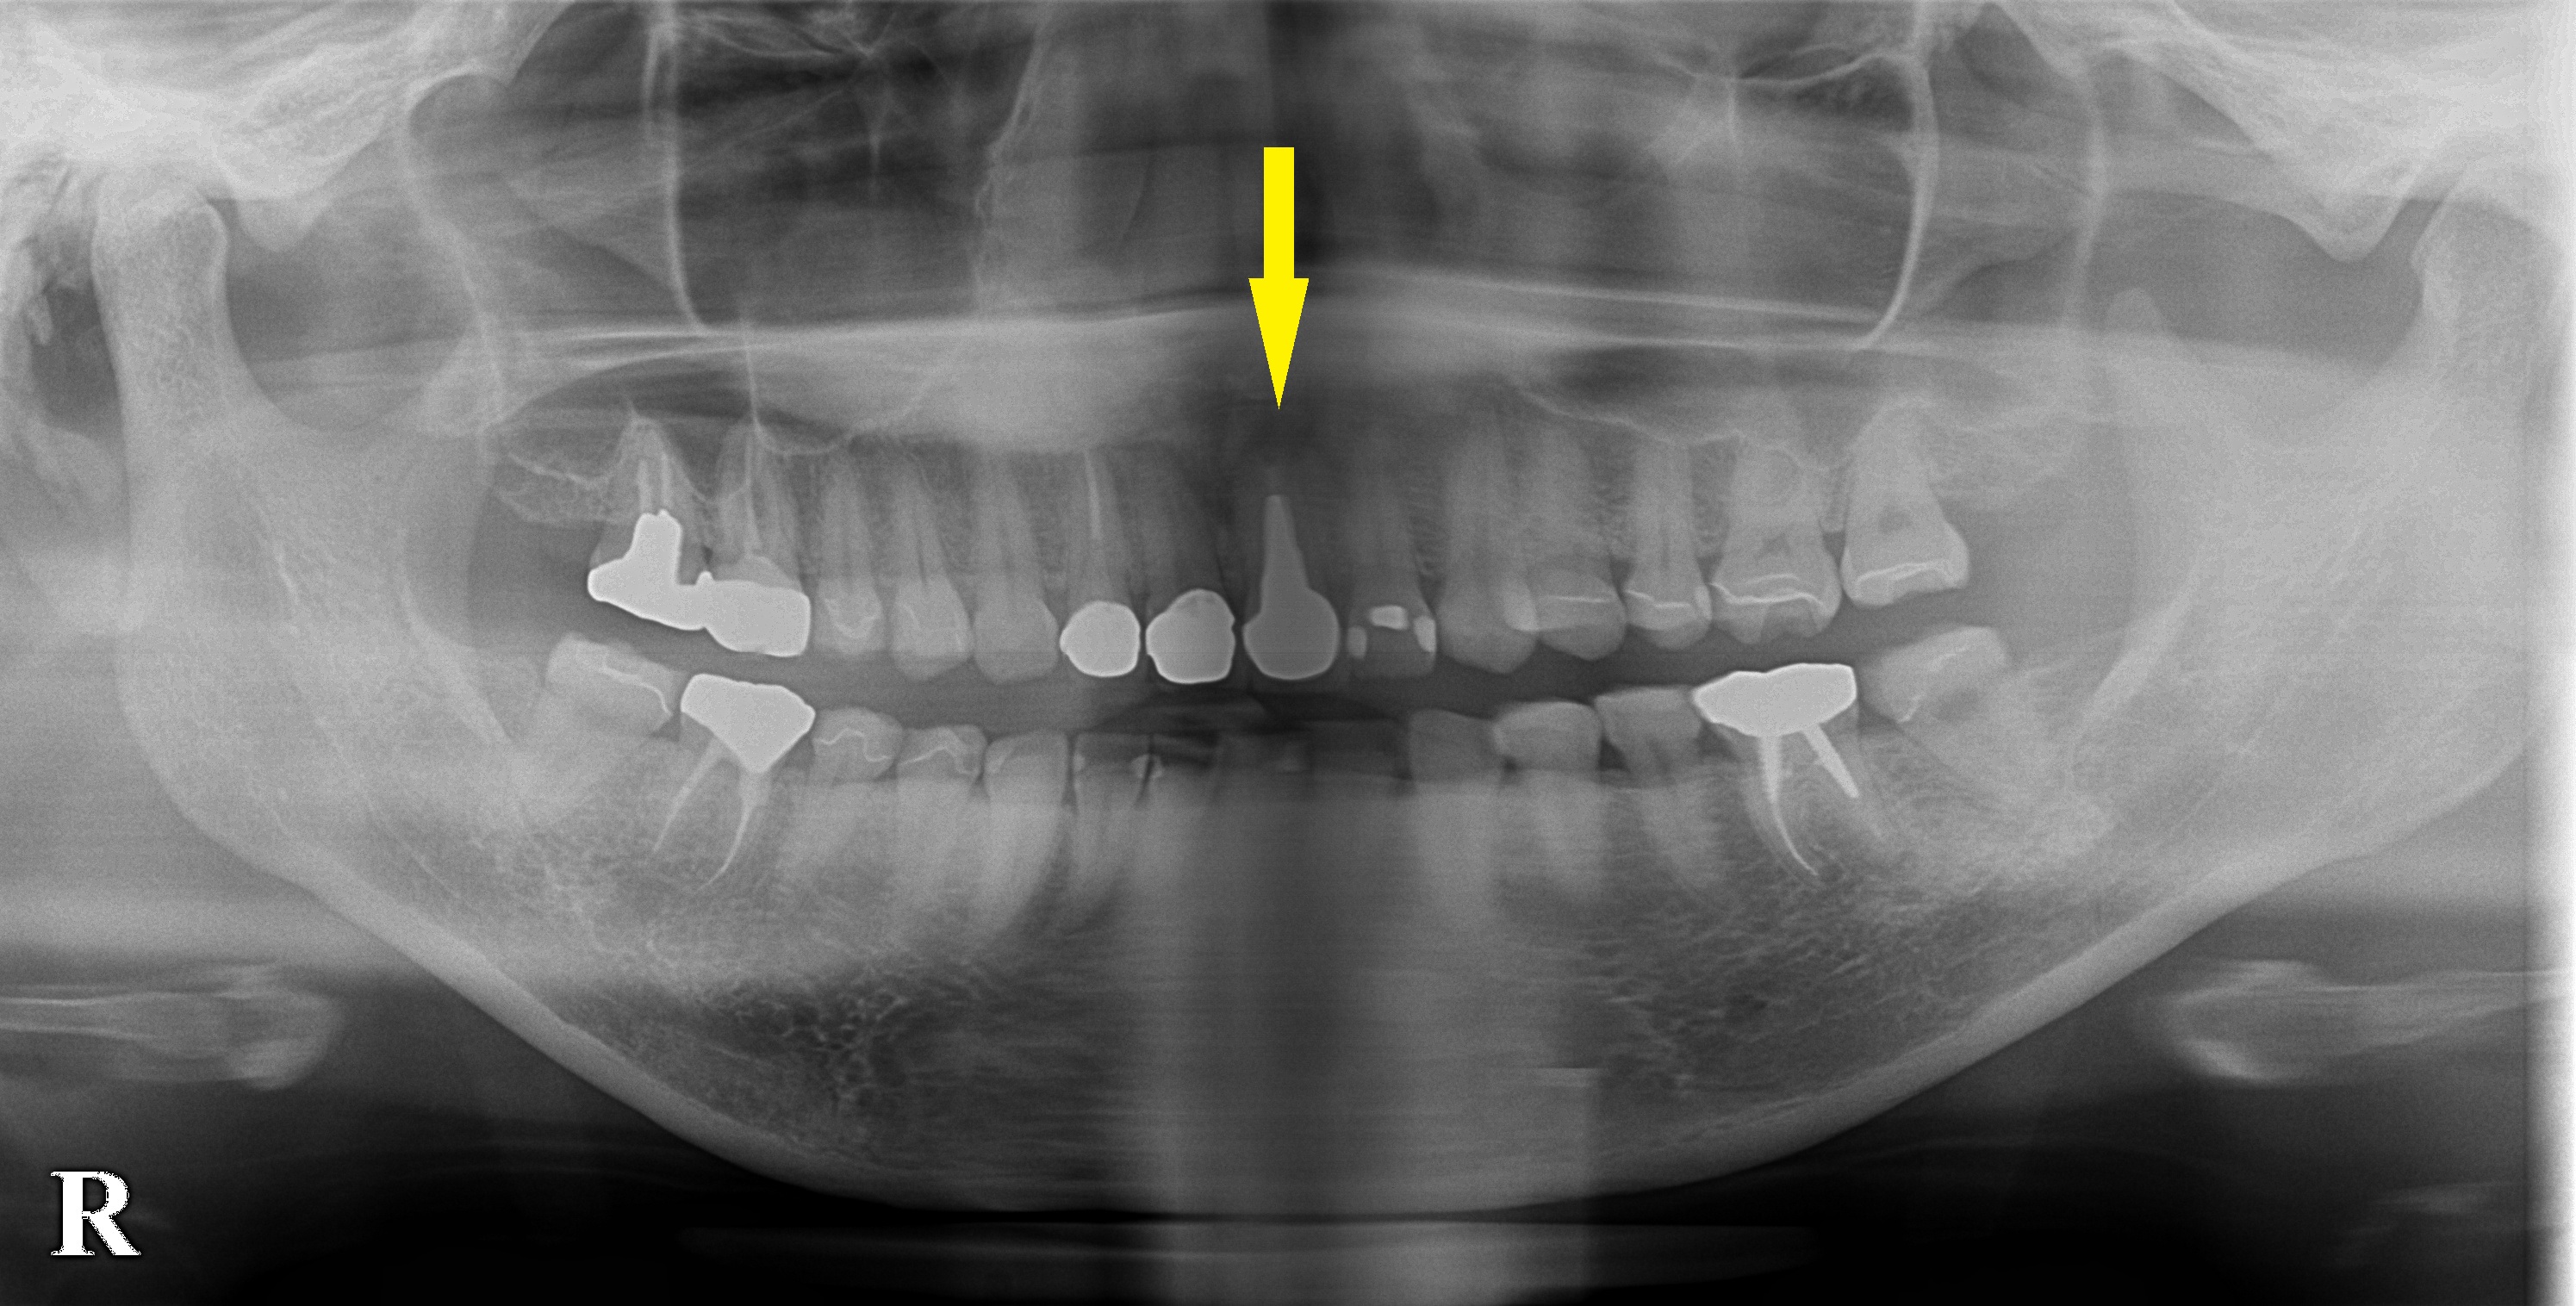

左上顎の前歯の歯根に膿がたまって、炎症を繰り返し、歯根も破折してしまっているので抜歯が必要と言われたそうです。

ブリッジではなくて、インプラント治療を希望されて相談においでになりました。

前歯ですので、抜歯即時インプラント埋入をお勧めしました。